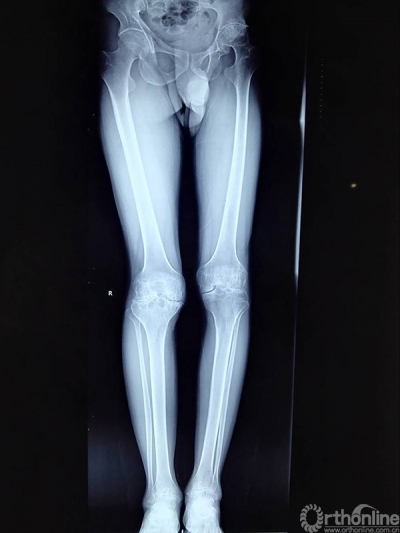

术前X片:双膝重度关节炎改变伴内翻畸形,左股骨头坏死伴关节僵直

术后X片:各关节屈伸度活动度良好,患者主诉疼痛改善